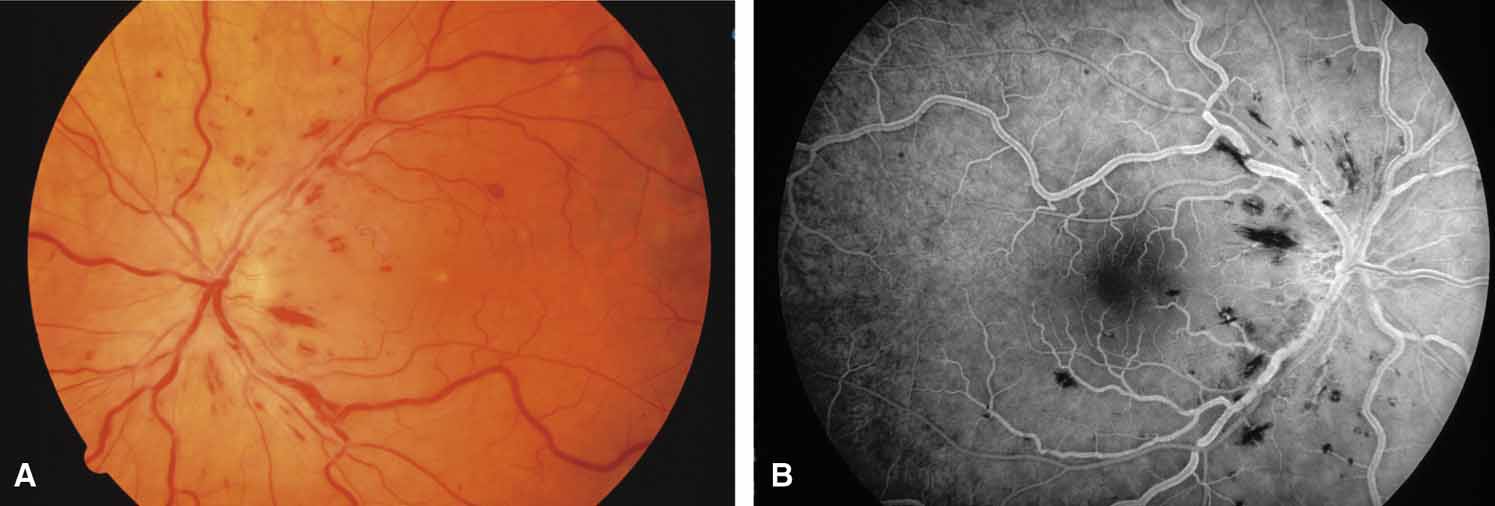

The possible association between retinitis pigmentosa and glaucoma dates back to 1862.11 Over the past century the reported glaucoma incidence has varied between 2.98% to 10% of all cases of retinitis pigmentosa.12,13 Of concern in all previous reports is the accuracy of the diagnosis of retinitis pigmentosa itself, a hereditary disease with diverse manifestations. Retinitis pigmentosa-like syndromes may mimic glaucomatous field loss, and the pattern of advancement of visual field loss in true retinitis pigmentosa may parallel that of typical open-angle glaucoma. Patients with undiagnosed retinitis pigmentosa may have subtle fundus findings, especially those with the sine pigmento form (Fig. 1). A clue to diagnosis is the disproportionate peripheral field loss in comparison to the degree of optic nerve cupping and rim pallor. Patients with atypical field loss and minimal optic nerve cupping should have an electroretinogram to exclude unsuspected retinitis pigmentosa.